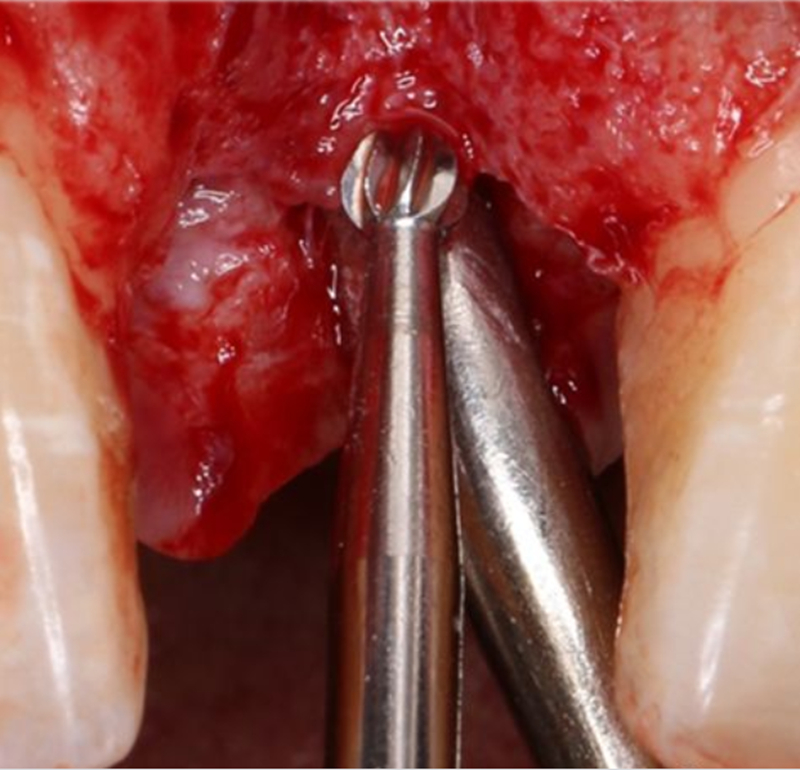

2.8mm 擴孔鉆按種植體軸向擴大窩洞△

在實時導(dǎo)航系統(tǒng)中,實時引導(dǎo)擴孔鉆按照術(shù)前設(shè)計種植體軸向及深度進行擴孔△